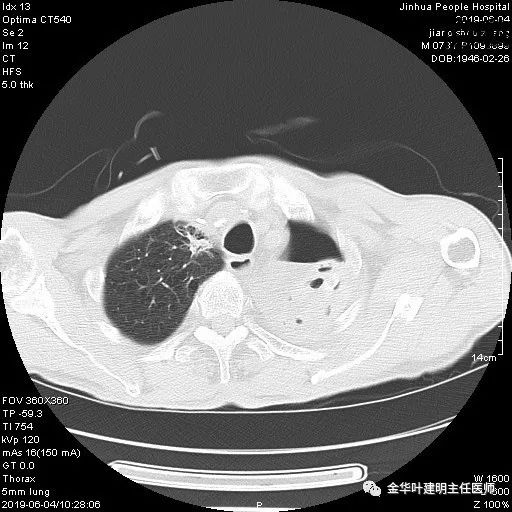

6.4上午:24小时引流出血性乳糜液1800毫升。是否再次手术进行右进胸胸导管结扎,抑或继续保守治疗非常纠结!压力非常大!!多方讨论会诊无法取得一致意见,但一般认为,引流量在1000毫升以上宜积极手术。情况与浙二医院范军强教授联系,请求指导,范教授认为左侧肺手术,损伤胸导管主干的机会较小,多数可保守治疗而愈。在他们的病例中,也有结扎胸导管后引流量仍无减少,效果并不能完全保证。建议可以考虑胸管夹管观察(因为淋巴管压力低,予以适当的压力,漏出量可能会明显减少),同时继续禁食,并静脉营养支持,引流管口可能会有渗液,注意更换敷料。与家属充分沟通后决定试夹管;这天血色素9.0 g/L;胸部CT复查示: